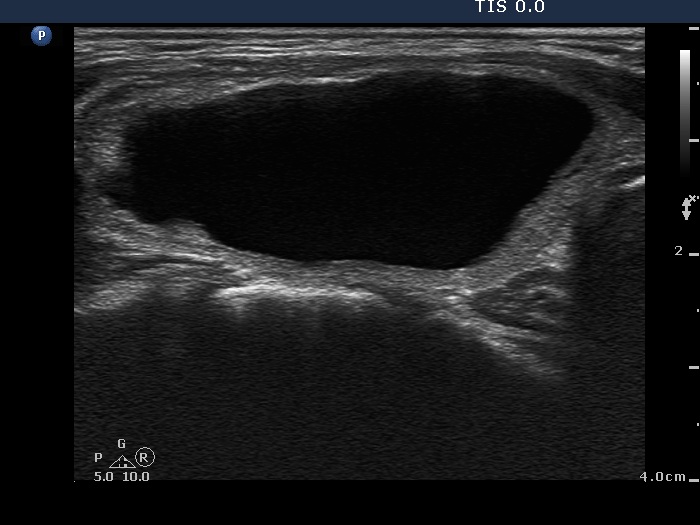

Ethanol sclerotherapy: other examples - Case 3: treatment of a gelatinous thyroid cyst

First session of therapy (ultrasonographic picture 2)

Right lobe, longitudinal scan.